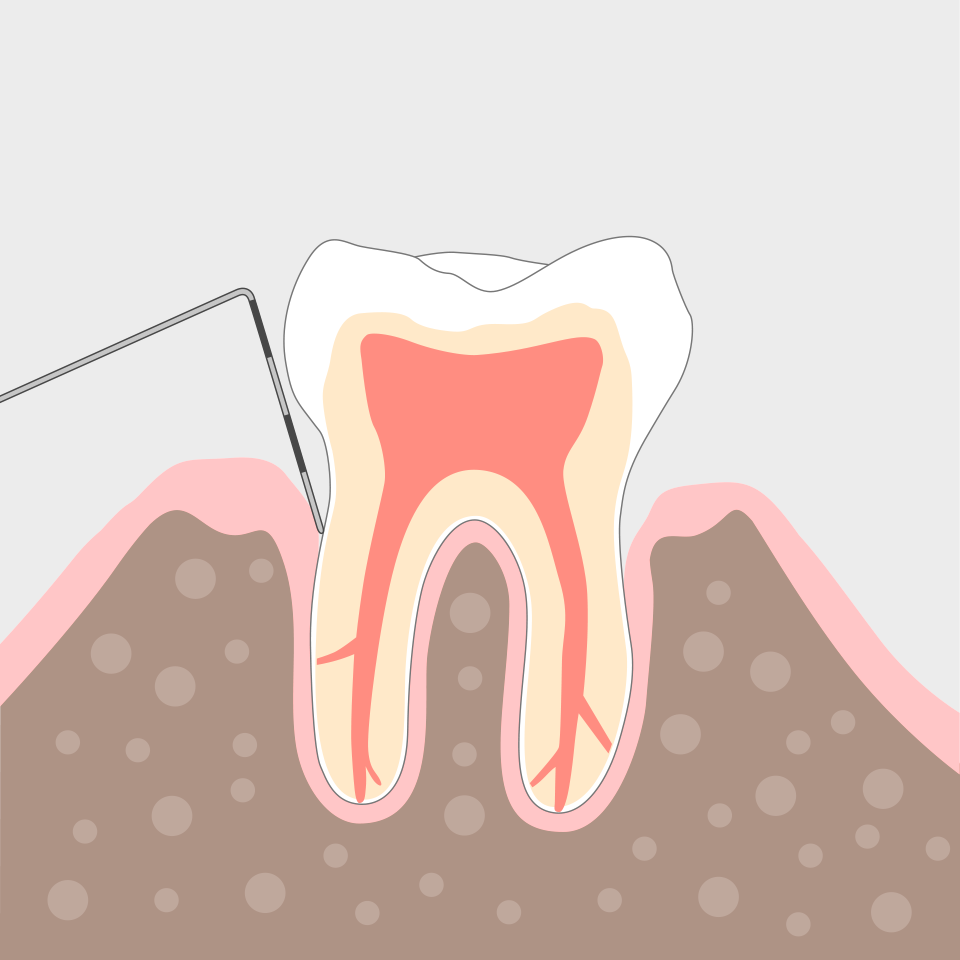

Mit modernen Behandlungsmethoden sorgen wir zunächst für gesunde Verhältnisse im Mund. Denn größtmögliche Keimfreiheit vor allem im Zahnbett ist die Voraussetzung dafür, dass die Entzündungen abheilen, und sich der Zahnhalteapparat (Parodontium) regenerieren kann. Dazu werden die schädlichen Bakterienablagerungen sorgfältig aus den Zahnfleischtaschen entfernt.

Die Behandlung zeigt schon bald erste Erfolge: Das Zahnfleisch wird wieder fest und rosig, das Zahnfleisch legt sich enger an den Zahn und die vertieften Taschen bilden sich zurück.

Wie hoch ist das Risiko einer erneuten Erkrankung? Das Wichtigste ist, diesen Heilungsprozess durch regelmäßige, professionelle Vorsorgebehandlungen (Prophylaxe) zu unterstützen. Risikopatienten – dazu zählen insbesondere Raucher und Diabetiker – sollten in kürzeren Intervallen, das heißt alle 3 bis 4 Monate an der Vorsorgebehandlung teilnehmen, um das Ziel Zahnerhalt dauerhaft sicher zustellen. Die Intervalle legen wir in Absprache mit Ihnen fest.